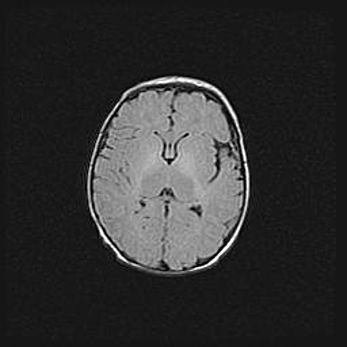

Множественные кисты обоих полушарий головного мозга, наибольшая из них в правой затылочной области. Ассиметричная атрофическая гидроцефалия.

Возраст: 7 месяцев

Вес: 5660 г

Пол: мужской

Окружность головы: 41,5 см

Срок гестации: 28-29 недель

Кисты головного мозга развиваются в результате многоочаговых некрозов вещества мозга и возникают вследствие перенесенной перинатальной инфекции, менингитов, энцефалитов, асфиксии, родовой травмы, расстройств мозгового кровообращения различного генеза. Образованию кист в веществе головного мозга плодов и новорожденных способствуют такие факторы, как высокое содержание в нем воды, недостаточная (или отсутствие) миелинизация и слабая астроглиальная реакция на повреждение.

Кисты могут сочетаться с гидроцефалией и другими поражениями головного мозга.